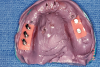

Fig 14. Maxillary arch with metal framework.

Figure 14